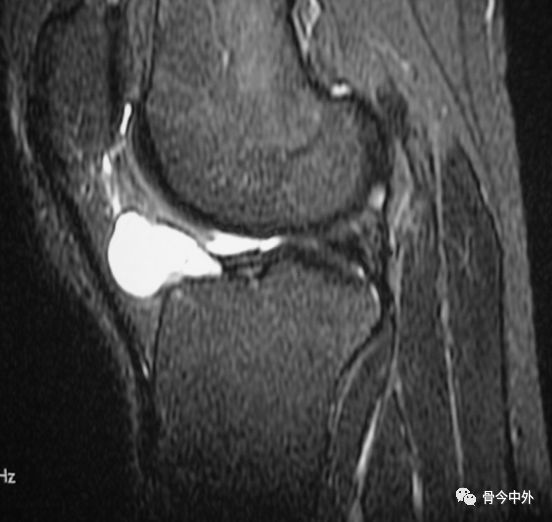

半月 板 水平 断裂

膝关节半月板损伤的磁共振 Mri 诊断 每日头条